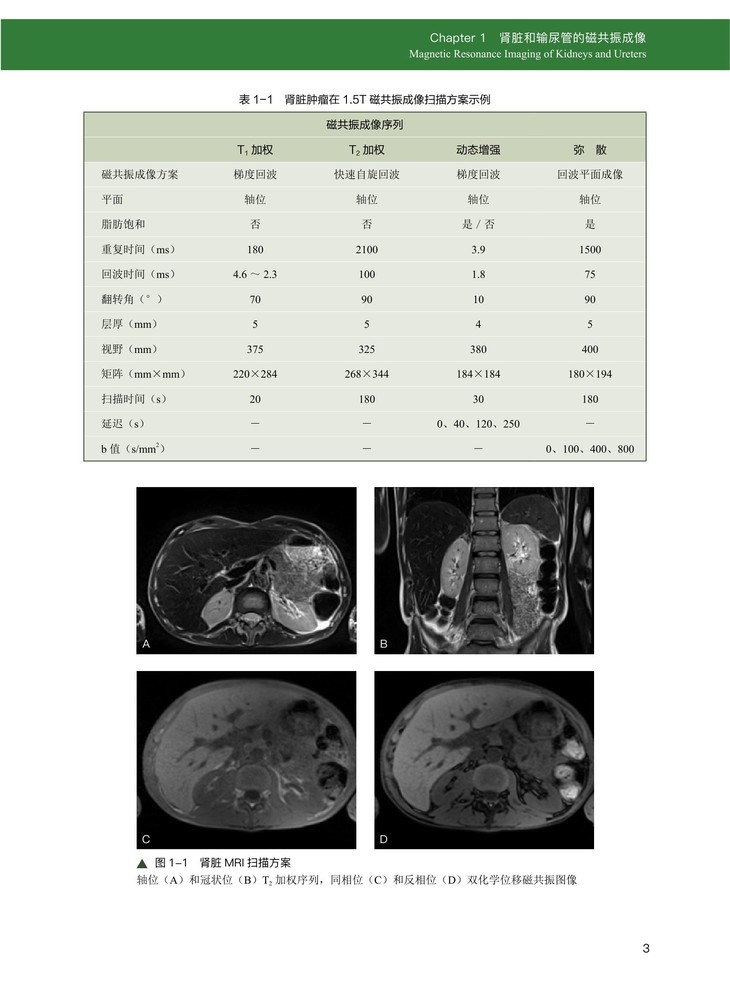

Chapter 1 肾脏和输尿管的磁共振成像

一、肾脏及输尿管 MRI 成像的具体技术规范